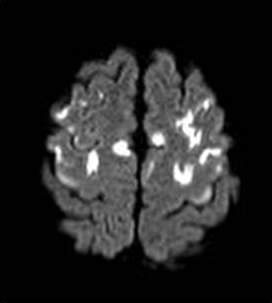

ГМ. Маркиафавы-Биньями болезнь. +

Маркиафавы-Биньями болезнь

Marchiafava, 1897, Bignami, 1903 – редко встречающийся вариант алкогольной энцефалопатии с патологистологичнски проявляющимся поражением (некрозом) мозолистого тела, образованием полостей в ткани мозга и развитием внутренней гидроцефалией. Клинически активная фаза заболевания длится от 2 до 6 лет, завершается она формированием глубокого слабоумия. В психотической стадии болезни наблюдаются слуховые и зрительные галлюцинации, апатия, депрессия, припадки, состояния возбуждения, спутанность сознания, картины псевдопаралича, а также разнообразные неврологические симптомы (тремор рук, дизартрия, абазия, арефлексия или гиперрефлексия, ослабление зрачковых реакций, изменение формы и величины зрачков и мн.др.). Лечение симптоматическое. Синонимы: Дегенерация мозолистого тела, Прогрессирующая алкогольная деменция